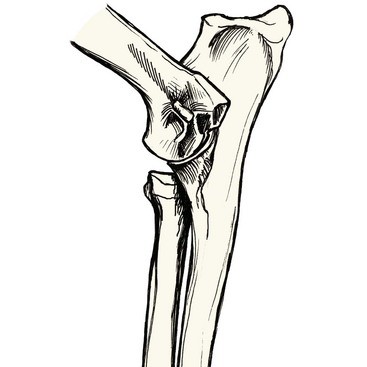

Joint Incongruity

Short Radius

Joint Incongruity: Abnormal conformation or mismatched growth between the three bones of the elbow at the level of the joint or distantly at the growth plates near the wrist.